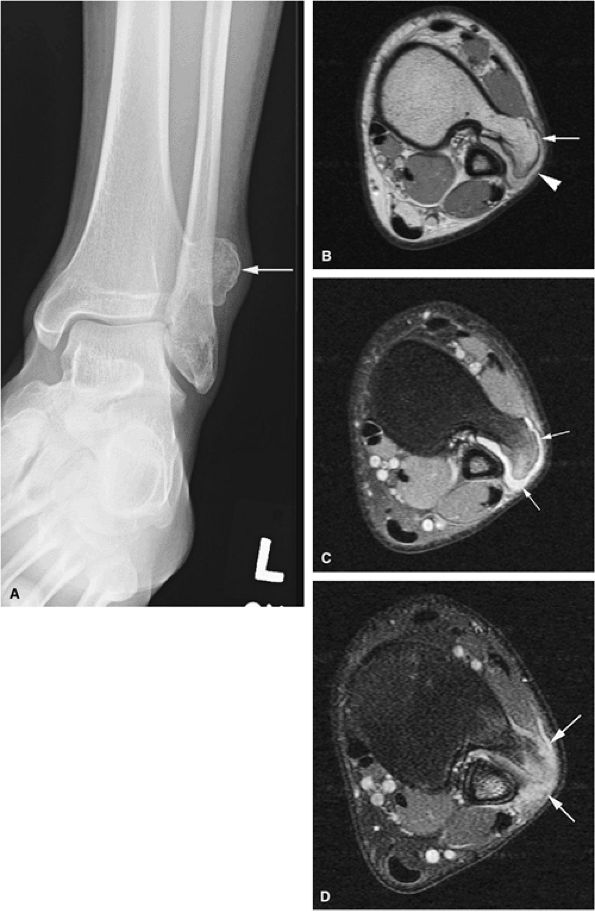

FIGURE 14-30 ● Bursa exostotica associated with a tibial osteochondroma. (A) Anteroposterior radiograph shows an osteochondroma arising from the distal tibia (arrow). (B) The osteochondroma (arrow) demonstrates continuity with the medulla cavity at the tibia. The bursa exostotica (arrowhead) is hyperintense on a proton density-weighted axial image. (C) On a fat-suppressed T2-weighted fast spin-echo image, the bursa exostotica is hyperintense (arrows). (D) Peripheral enhancement (arrows) is seen on a fat-suppressed T1-weighted axial image after administration of intravenous gadolinium.